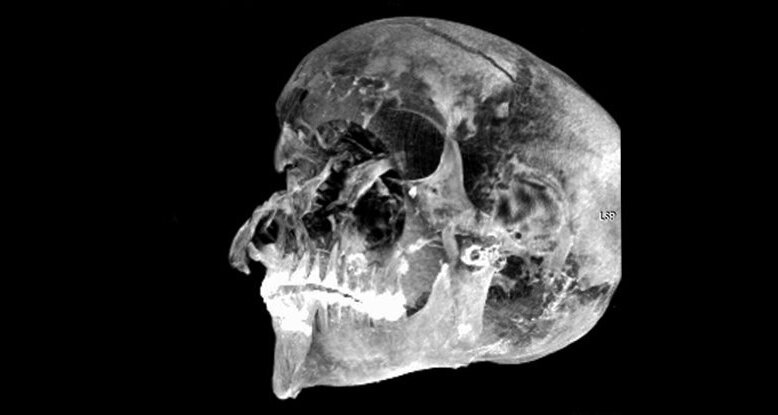

Останки Секененра были впервые обнаружены в 1881 году, а обследования в 1886 и 1906 годах показали, что при жизни он получил серьезные травмы головы. В 1960-х рентгеновские снимки выявили пять отдельных травм на его черепе, но нигде больше. Вдобавок ко всему его бальзамирование, казалось, было произведено очень наспех. Как ни странно, для сохранения тела не использовались соли, мозг оставался на месте, а в черепе не было ткани.